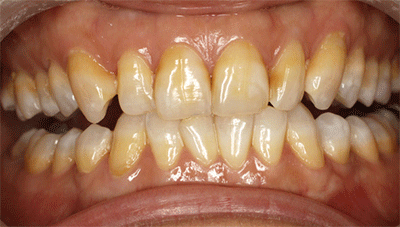

氟斑牙|瓷贴面修复——术前照片

术前正面照